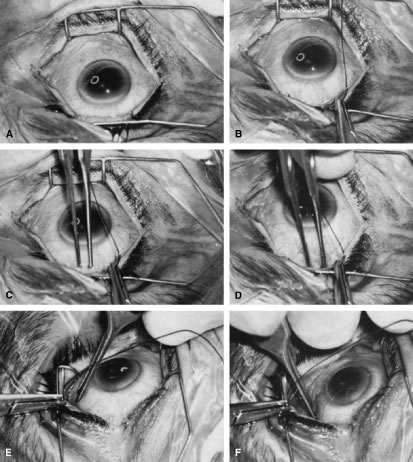

| Glaucoma surgery is best performed under the operating microscope. In some

the cornea is covered. The surgical anatomy of the anterior chamber angle in an average eye is shown in Figure 4A and B. Landmarks will differ markedly in eyes that have abnormalities. In the myope, the space between the anterior limbus and the iris root is greater; in the hyperope, it is less. An incision at the corneoscleral sulcus may enter the anterior chamber far anterior to the trabecular meshwork in the myope but may enter the posterior chamber in the hyperope. Because glaucoma in infants is rare, its surgical treatment is not discussed in detail. However, guarded filtration procedure is described later and may be employed with satisfactory results in many patients with congenital glaucoma (trabeculodyspenesis). PREOPERATIVE CARE The reader should refer to the earlier section of this chapter on evaluation of the person. The goal is to move the patient from conditions auguring failure toward those promising success. Obviously, many factors cannot be changed. In the simplest terms, the healthier the eye and the less likely it is that scarring will develop when the eye is injured, the greater the chance for success. Preoperative care is discussed in greater detail in the sections that describe the operative procedures. Many people take aspirin products routinely. Aspirin comes in many forms, and it is part of many compounds. Because it predisposes patients to bleeding, it should be discontinued, if prudent, 2 weeks before surgery. Most people who are taking aspirin are taking it for relatively unimportant indications; some simply may have heard that aspirin can help prevent heart attacks. However, in some patients, aspirin may be an important part of treatment, and discontinuation of the aspirin must be coordinated with the physician who ordered the aspirin. Wherever feasible, it should be discontinued preoperatively. Other agents also predispose patients to bleeding, for example, dipyridamole and anticoagulants, such as dicumarol. These agents should be discontinued an appropriate time before surgery to allow the blood to return to a normal clotting state. Some patients may have to take heparin instead of dicumarol at the time of surgery. This substitution must be individualized and coordinated with the physician managing the patient's anticoagulants. PARACENTESIS A paracentesis should be part of virtually all intraocular glaucoma surgical procedures. This opening in the cornea facilitates management of complications such as bleeding or flat anterior chamber; allows deepening of the anterior chamber at the time of surgery; provides an entry for acetylcholine or sodium hyaluronate; allows the surgeon to determine at the time of surgery how much filtration, if any is occurring through the guarded filtration procedure or sclerostomy; permits safe development of a bleb at the conclusion of surgery; and allows the surgeon to detect whether any tears or leaks are present in the conjunctival flap. The major risk of the procedure is that it may damage the lens. This damage can be avoided by making sure that the instrument used to develop the paracentesis never points toward the lens; holding the instrument parallel to the iris surface eliminates the risk of damaging the lens. Fixation of the globe is critical. The point of fixation should be directly in line with the intended direction of the paracentesis. If the paracentesis is to be made at the 10 o'clock position, extending exactly inferiorly, the sclera should be held directly superior to the 10 o'clock position (Fig. 5). If the surgeon prefers a horizontal paracentesis, starting at the 3 o'clock position, then the globe must be fixated precisely at the 3 o'clock position. An instrument with fine teeth provides good fixation. Examples are the Bonn or Barraquer-Colibri fine-toothed forceps. The tips should be separated only slightly, approximately 1 mm, and then pressed hard against the sclera. Conjunctiva, Tenon's capsule, and episclera are not adequate sites for fixation. We prefer to use a new, sharp, short, disposable 27-gauge needle on a 2- or 5-ml syringe. The needle is held, bevel up, absolutely parallel to the iris surface. In an eye with an iris bombe or a flat anterior chamber, the needle actually may be pointing anteriorly. The tip of the needle is placed against the cornea in the desired position, and the globe is pulled by the fixating hand in the direction opposite to that in which the needle is pointing. For example, if the needle is held horizontally, at the 3 o'clock position of the left eye, then the sclera is grasped at the 3 o'clock position and pulled laterally (temporally) (see Fig. 5). The needle tip enters the cornea. If there is normal or elevated pressure and the chamber is deep, the needle penetrates the cornea after making a paracentesis that is approximately 1 to 2 mm long. If the eye is soft or the chamber is shallow, the needle remains in the cornea and does not penetrate the anterior chamber. This position is desirable in cases in which the cornea is thin, such as in the buphthalmic eye. If the intracorneal track is longer than 2 mm, then the needle and syringe are depressed back toward the apex of the orbit; they are depressed toward the floor of the operating room (see Fig. 5, top right). The tip of the needle must not be angled toward the iris-lens; it must be kept parallel to the iris. As the needle and syringe are pushed toward the floor, the needle changes the curvature of the cornea, permitting it to enter the anterior chamber when advanced. The needle is advanced by a combination of pulling the globe and pushing the syringe. The importance of firm fixation and of introducing the needle against traction provided by the fixation must be stressed. Also, it is essential that the needle not be angled toward the iris, but kept parallel to the iris surface. Once the needle enters the anterior chamber, it is more clearly visible than when it is intracorneal (see Fig. 5, bottom right). The tip is advanced carefully about 1 to 3 mm, until the surgeon is sure that the endothelium has been completely penetrated. The needle is then withdrawn. If the paracentesis has been made with a no. 25 needle, a no. 30 blunt-tipped needle can be introduced later with ease. If the cornea is especially thin or if the surgeon wishes the fit to be especially tight, a 30-gauge needle should be used for the paracentesis. When re-entering the paracentesis track, the blunt needle must be directed exactly parallel to the original track and must hug the posterior (internal, deep) aspect of the track. Often, the neophyte struggles unnecessarily to get the no. 30 blunt-tipped needle into the anterior chamber through a no. 27-size paracentesis. However, when the blunt-tipped 30-gauge needle is angled in the direction of the floor, that is, toward the iris, and slid along the internal aspect of the paracentesis, it enters gracefully. Alternatively, use a sharp 27-gauge needle for the paracentesis and a sharp no. 30 needle for later entry. USE OF SLIP KNOTS AND RELEASABLE SUTURES The use of a slip knot is helpful in achieving the desired level of tightness of the scleral flap in a guarded filtration procedure. Slips knots also have the advantage of being easier to bury than the usual surgeon's knot. They cannot be used to close incisions under tension, but are appropriate for almost all other situations. We use them routinely. Figure 6 illustrates the method of tying slip knots. See p. 24 for a discussion of releasable sutures (Fig. 7). IRIDECTOMY Iridectomy deserves separate treatment in this chapter because, with rare exceptions, its basic purpose is different from that of all other glaucoma surgery. Iridectomy often is performed not to lower IOP but to correct an anatomic aberration, narrowness of the anterior chamber angle (Fig. 8). It is important to explain to the patient why the iridectomy is recommended. Patients usually conclude that glaucoma surgery has as its purpose the lowering of IOP, and unless enlightened to the contrary, most patients anticipate that IOP will be lower after iridectomy. Diagnosis and Classification An extensive description of the diagnosis and classification of the angle-closure glaucomas cannot be given here.1,43 However, the essential component in the diagnosis of the angle-closure glaucomas, gonioscopy, must be mentioned. Differentiation between optical contact and actual adhesion between the iris and the cornea cannot be made without the use of indentation gonioscopy; therefore, the correct diagnosis of the angle-closure glaucomas demands the appropriate use of a gonioscopic lens that can be used in indentation gonioscopy8,44 (Fig. 9). We prefer the Zeiss four-mirror lens on an Unger handle. For the diagnosis of angle-closure glaucoma to be certain, the ophthalmologist must be certain that the symptoms could only be the result of angle closure and that the anterior chamber angle actually has closed. Thus, the search for peripheral anterior synechiae, characteristically between the 10 and 2 o'clock positions of the eye, assumes great significance. Peripheral iridectomy is described in moderate detail because it is our opinion that the general ophthalmologist should still be fully competent in performing a standard surgical iridectomy. Nd:YAG laser iridotomy is clearly the procedure of choice in patients needing an iridotomy. However, it is not always possible. In patients in whom the cornea does not become sufficiently clear to allow a laser iridotomy, an incisional surgical iridectomy becomes necessary. In addition, incisional iridectomy may be necessary in some patients with a diagnosis of pupillary block glaucoma in whom a persistent, patent peripheral iridotomy cannot be achieved with laser techniques. Preoperative Care Most attacks of acute primary angle-closure glaucoma can be treated medically. The longer the attack, the higher the pressure, the more the eye has been damaged, and the less likely the patient is to be harmed by the medications used to treat the attack, the more vigorous the treatment should be. When the attack is brief, the inflammatory signs minimal, and the pressure relatively low, pilocarpine 1% every 5 minutes for four doses often is adequate. Apraclonidine 1% often is helpful in treating patients with high IOP or in cases in which lowering IOP is not expected to be accomplished with the use of pilocarpine alone. When treatment must be maximal, the following routine may be followed: pilocarpine 1% every 5 minutes for four doses; timolol 0.5% immediately and again in 1 hour; apraclonidine 1% immediately; acetazolamide 500 mg intravenously; and an osmotic agent (isosorbide, 30 mg/kg body weight in routine cases; mannitol 20%, 70 ml/kg body weight intravenously in the nauseated patient who can tolerate a large sudden increase in blood volume; or anhydrase glycerol orally, 1 ml/kg body weight in the patient who can take oral medication but is likely to have urinary retention). Topical steroids are appropriate if the eye is inflamed. Occasionally, forceful compression of the anterior chamber with an instrument such as the Zeiss four-mirror gonioprism can push the angle open and help to end the angle-closure attack. Once the attack has been stopped, it is helpful to allow the eye to quiet before proceeding with the iridectomy. Weak pilocarpine administration, such as 1% two or three times a day and aqueous suppressants, such as timolol and acetazolamide, should be continued until the time of surgery. If surgery is indicated on the fellow eye, it may be appropriate to perform an iridectomy on that eye while waiting for the involved eye to quiet. Pilocarpine should be used with caution in both the involved eye and the fellow eye because it can predispose the eye to angle closure by increasing the degree of papillary block or causing the lens-iris diaphragm to move anteriorly. Occasionally, it is impossible to break an attack. In such cases, it is advisable to proceed with surgery promptly, despite the presence of high IOP. Here, a retrobulbar injection of anesthetic agent is appropriate and may help lower the IOP. If unsuccessful, the pressure will be brought down easily by paracentesis at the time of surgery. When a peripheral iridectomy is performed, the pupil should be as small as possible. The use of mild pilocarpine is an easy, effective approach. In cases in which the IOP remains elevated or the sphincter is nonfunctional, however, reducing the size of the pupil may be difficult. Multiple instillations of pilocarpine are not recommended in such cases. Usually, they only make the patient systemically ill and the eye inflamed; they do not reduce the size of the pupil. If the sphincter is functional, the pupil will contract quickly once the IOP has been lowered. On the other hand, if the surgeon is planning to perform a sector iridectomy, it is best to have the pupil dilated as widely as possible. Such a sector iridectomy probably is the preferred procedure in patients with severe iris atrophy, a dilated fixed pupil, or a cataract that is limited to the visual axis. Operative Technique Adequate anesthesia for surgical iridectomy performed with a blade is provided by topical administration of an agent such as proparacaine 0.5% eye drops. Tetracaine also is effective, but it appears to have a slightly more irritating effect on the corneal epithelium. Proparacaine 0.5% given approximately every 30 seconds for ten doses 10 minutes before the procedure and then followed by about five instillations after the eye has been prepared and draped, immediately before the surgery, almost always gives satisfactory anesthesia. It is even possible to place a superior rectus bridal suture without causing undue discomfort. In most cases, it is preferable to perform a facial nerve block with a modified O'Brien block.45 This approach allows easier and more comfortable placement and retention of the speculum. Because the procedure usually lasts only about 5 to 15 minutes, a short-acting injection anesthetic, such as lidocaine, is appropriate. The relevant anatomic considerations are shown in Figure 4A and B. The operative technique is shown in Figure 10. The iridectomy should be performed so that the only instruments that enter the anterior chamber are the needle that is used to develop a paracentesis track and the tip of the blade that is used to make the corneoscleral incision. The advantages of the paracentesis so greatly outweigh the minute risks associated with it that we believe that it should be performed routinely. The technique is described in detail earlier in this chapter and is illustrated in Figure 5. When properly performed, this procedure is virtually without risk, even in patients with extremely shallow or flat anterior chambers. Without such an opening into the anterior chamber, the integrity of the incision cannot be tested, blood in the anterior chamber cannot easily be irrigated away, and chamber deepening cannot readily be performed. To prevent the tip of the knife used to develop the corneoscleral incision from damaging the iris or lens, it is preferable to use a broad blade, such as the no. 67 Beaver blade. Multiple small scratches are made, with the surgeon verifying that the depth of the incision is uniform from end to end. Some surgeons prefer an anteriorly shelved incision because it tends to close more easily; in the past, many surgeons did not place a suture through this type of incision. However, a perpendicular incision allows the iris to prolapse more readily, gives better visualization, and facilitates the procedure. The availability of fine suture material allows tight closure of the incision with minimal irritation or difficulty. The scissors used to perform the iridectomy should be sharp and should be tested immediately before the procedure to ensure their proper operating condition. We prefer the use of a preplaced suture, as seen in Figure 10. This approach provides a clearer view of the process of creating the corneal incision, it aids in prolapsing the iris, and it allows for immediate closure with a suture that the surgeon knows is perfectly placed. Any of a number of sutures is satisfactory. Absorbable polyglactin [Vicryl (Ethicon, Somerville, NJ)] works well and has the advantage of not requiring removal. A 9-0 nylon suture also is satisfactory; it is thick enough to be used to retract the tissue yet fine enough to be well tolerated. The small fornix-based flap can be closed by stretching it toward one side, especially if a radial relaxing incision approximately 2 mm long and extending from the limbus has been performed (Fig. 11). This closure can be done with the same suture used to close the corneoscleral incision, or it can be coapted with the wet-field cautery. If the scissors performing the iridectomy are held as shown in Figure 12 the iridectomy will tend to be broad based but will remain basal, reducing the chance that the patient will have a disturbing sense of double vision postoperatively. It is important to stress that in a properly performed iridectomy, it is not necessary to insert the iridectomy forceps into the anterior chamber. To do so unjustifiably increases the risk of damage to the cornea, lens, and zonules. If a fine-toothed forceps such as a Bonn forceps is employed, the surgeon must be careful to pull the iris out of the anterior chamber far enough to ensure that the iridectomy will he penetrating. A nontoothed forceps, such as a McPherson tying forceps, offers the relative advantage of providing a less secure grip on the iris, requiring the surgeon to grasp more tissue. The disadvantage, however, is that control of the tissue is less certain, and the forceps must be inserted further into the incision.